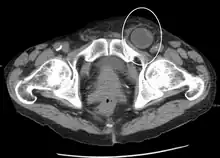

In the diagnosis of abdominal hernias, imaging is the principal means of detecting internal diaphragmatic and other nonpalpable or unsuspected hernias. Multidetector CT (MDCT) can show with precision the anatomic site of the hernia sac, the contents of the sac, and any complications. MDCT also offers clear detail of the abdominal wall allowing wall hernias to be identified accurately.[9]

Femoral

Femoral hernias occur just below the inguinal ligament, when abdominal contents pass into the weak area at the posterior wall of the femoral canal. They can be hard to distinguish from the inguinal type (especially when ascending cephalad): however, they generally appear more rounded, and, in contrast to inguinal hernias, there is a strong female preponderance in femoral hernias. The incidence of strangulation in femoral hernias is high. Repair techniques are similar for femoral and inguinal hernia.